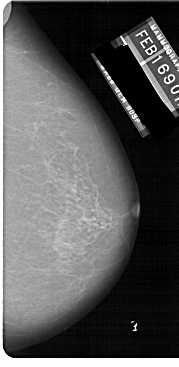

A_1149_1.RIGHT_MLO

RIGHT_MLO LINES 5491 PIXELS_PER_LINE 2776 BITS_PER_PIXEL 12 RESOLUTION 43.5 NON_OVERLAY